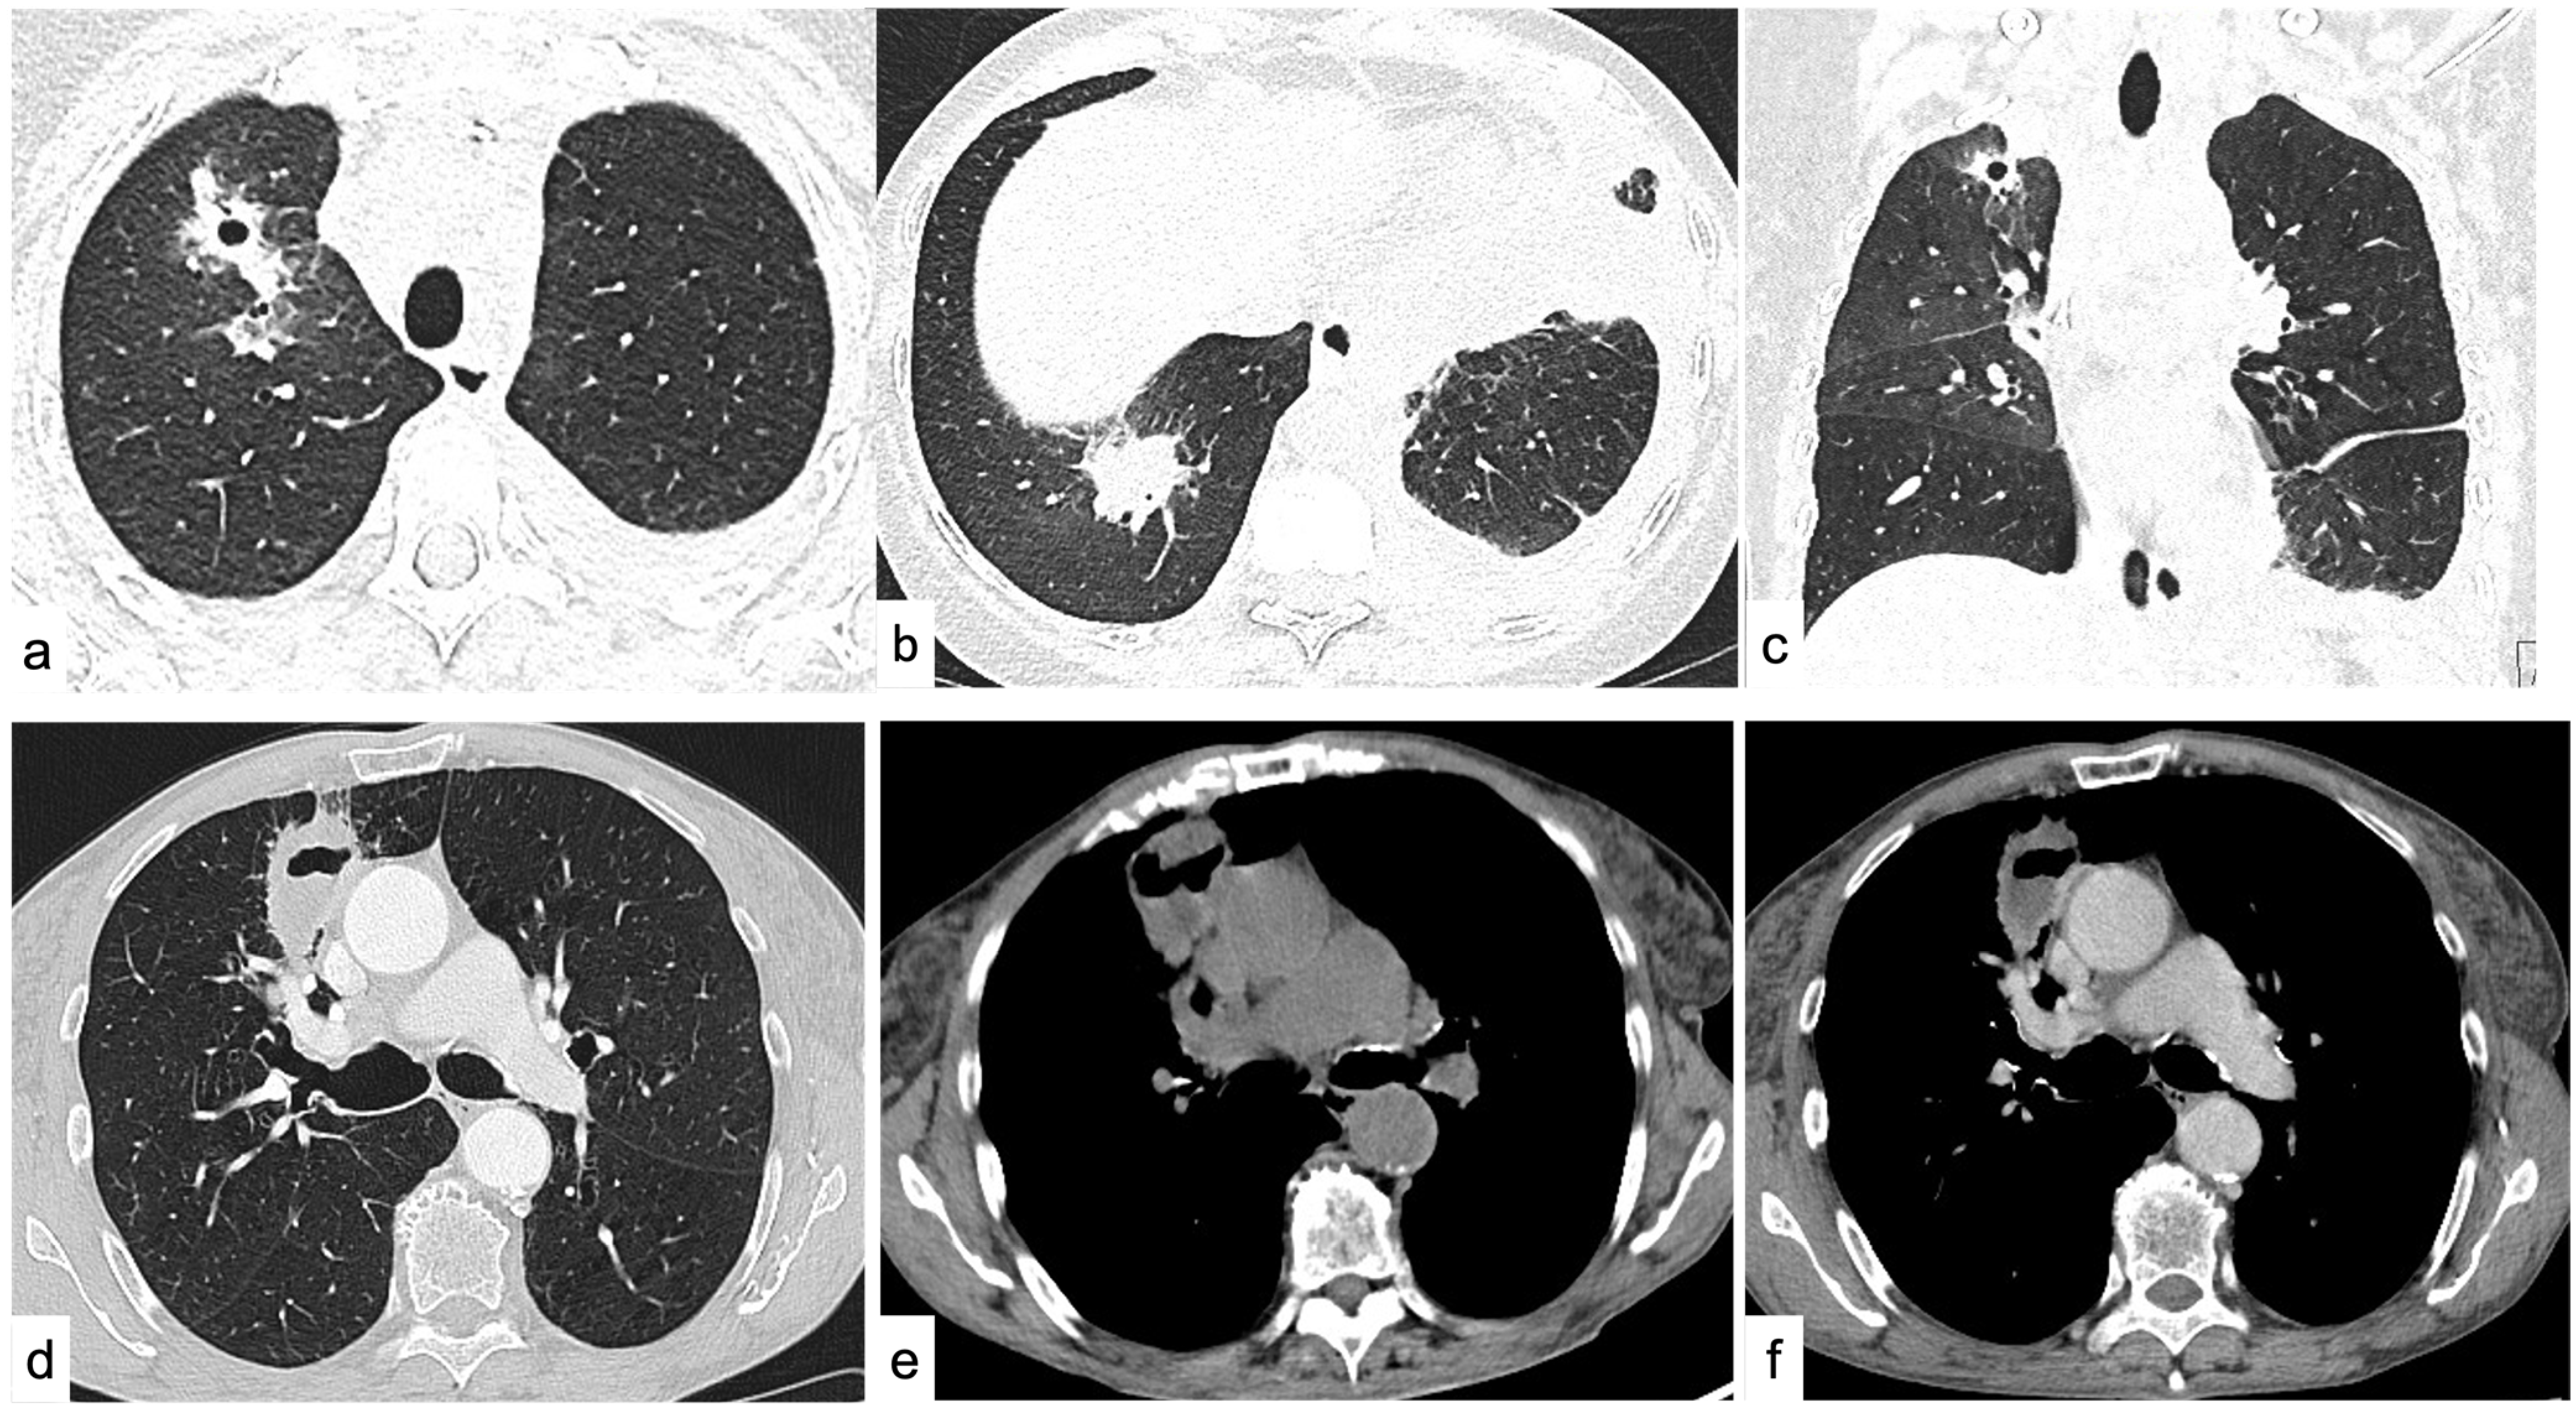

4.1.1. Density

4.1.2. Shape

4.1.3. Margins

4.1.6. Cavitations and Cysts

4.2. Diffuse Lung Disease